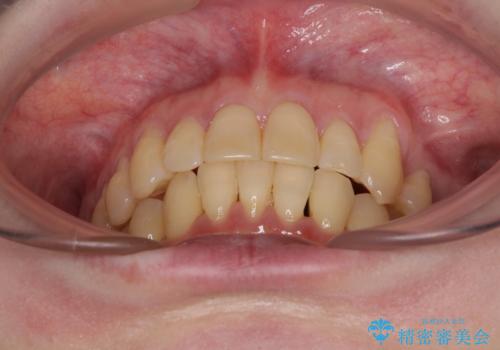

八重歯と先天欠損の歯列 ワイヤー矯正ですっきりと

- 八重歯と正中のズレを気にして来院された患者様です。

上顎左側が八重歯になっており、上顎正中が左側にずれていました。

上顎左側の第一小臼歯を抜歯し、補助装置を用いて正中位置を改善しながら八重歯を解消していくこととしました。

下顎前歯が1本欠損していたため、上下正中の位置が合わせるという目標はなく、鼻筋に上顎正中を合わせていくように移動を行いました。